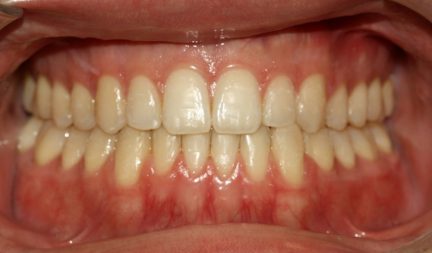

Classe III, béance, arcades étroites, arcades asymétriques, déviation médiane maxillaire, déviation médiane mandibulaire, décalage médian, encombrement, rotations, espacement, diastème

Mésialisation, courbe de Spee nivelée, égression, expansion, rétraction, vestibulo-version, fermeture de l'espace, traitement de phase II, élastiques : Classe III

- Relation de classe I obtenue

- Guidage fonctionnel des canines des deux côtés

- Surplomb et recouvrement normaux obtenus

- Surplomb amélioré

- Amélioration significative du surplomb

- Lignes médianes coïncidentes

- Bonne inclinaison axiale des incisives

- Courbe de Spee nivelée

- Arches alignées et coordonnées

- Forme de l'arcade améliorée

- La ligne de sourire esthétique a été obtenue

- Cas où tous les objectifs du traitement ont été atteints

- Des arcades harmoniques ont été obtenues

État initial

État final